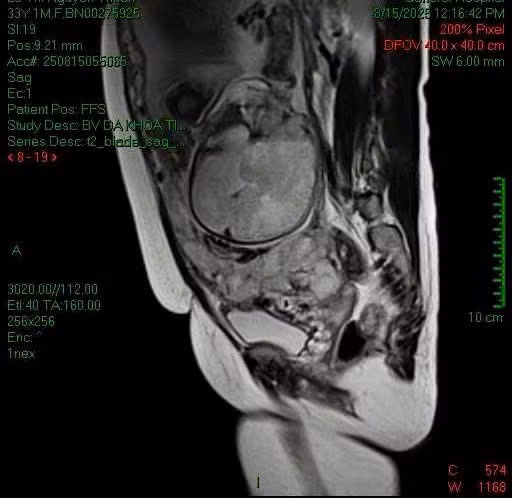

Qua siêu âm và MRI, bác sĩ xác định, đây là trường hợp bị nhau cài răng lược thể percreta; Tình trạng bánh nhau tăng sinh mạch dữ dội; Các gai nhau xuyên qua cơ tử cung vào nền dây chằng rộng và bàng quang.

Nhau cài răng lược xâm lấn bàng quang trên phim chụp - Ảnh BVCC